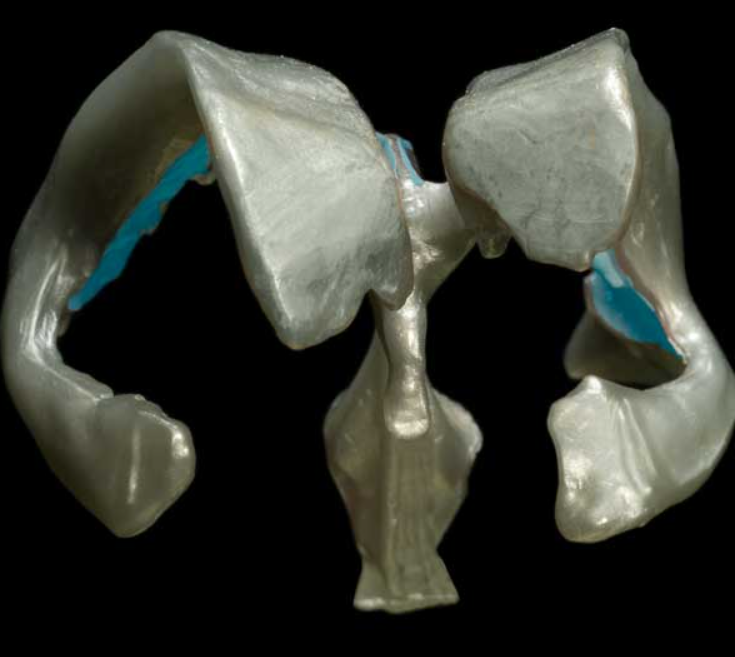

falx cerebri

falx cerebelli

tentorium cerebelli